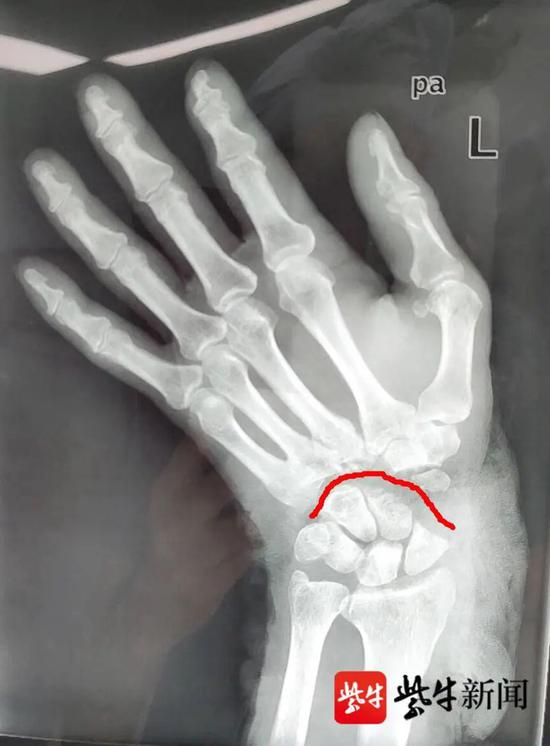

“患者到达急诊后,我们冲洗、固定、包扎伤口后,赶紧为他做了X光片检查,检查结果显示其腕掌关节90%以上离断,伤势非常严重。”江大附院急诊科手外科副主任医师尹其翔告诉记者,肢体离断后最佳抢救时间是6~8小时内,越早救治成功率越高,而电锯伤是高能量损伤,再植手术难度大、风险也高。

下午4点55分,手术正式开始。尹其翔介绍,断腕再植的手术难度主要在于吻合量大,需要将断离的骨关节、神经、动静脉、肌腱等一一进行匹配和重建,对医生技术和耐力都是一个考验。其手术步骤如下:

一通过克氏针稳定腕关节,二修补肌腱,三吻合血管,四吻合神经,五修复软组织,六外固定支架,固定腕关节。

“肌腱、神经和血管的吻合是个精细活儿,平均吻合一根肌腱、神经大概需要20分钟,血管则耗时更久,大约需要40分钟左右。”尹其翔说,虽然很耗时,但也要医生分秒必争,因为离断肢体长时间缺血,可能导致组织坏死。这次断腕再植术中,医生共吻合肌腱17根,神经3根,血管2根。